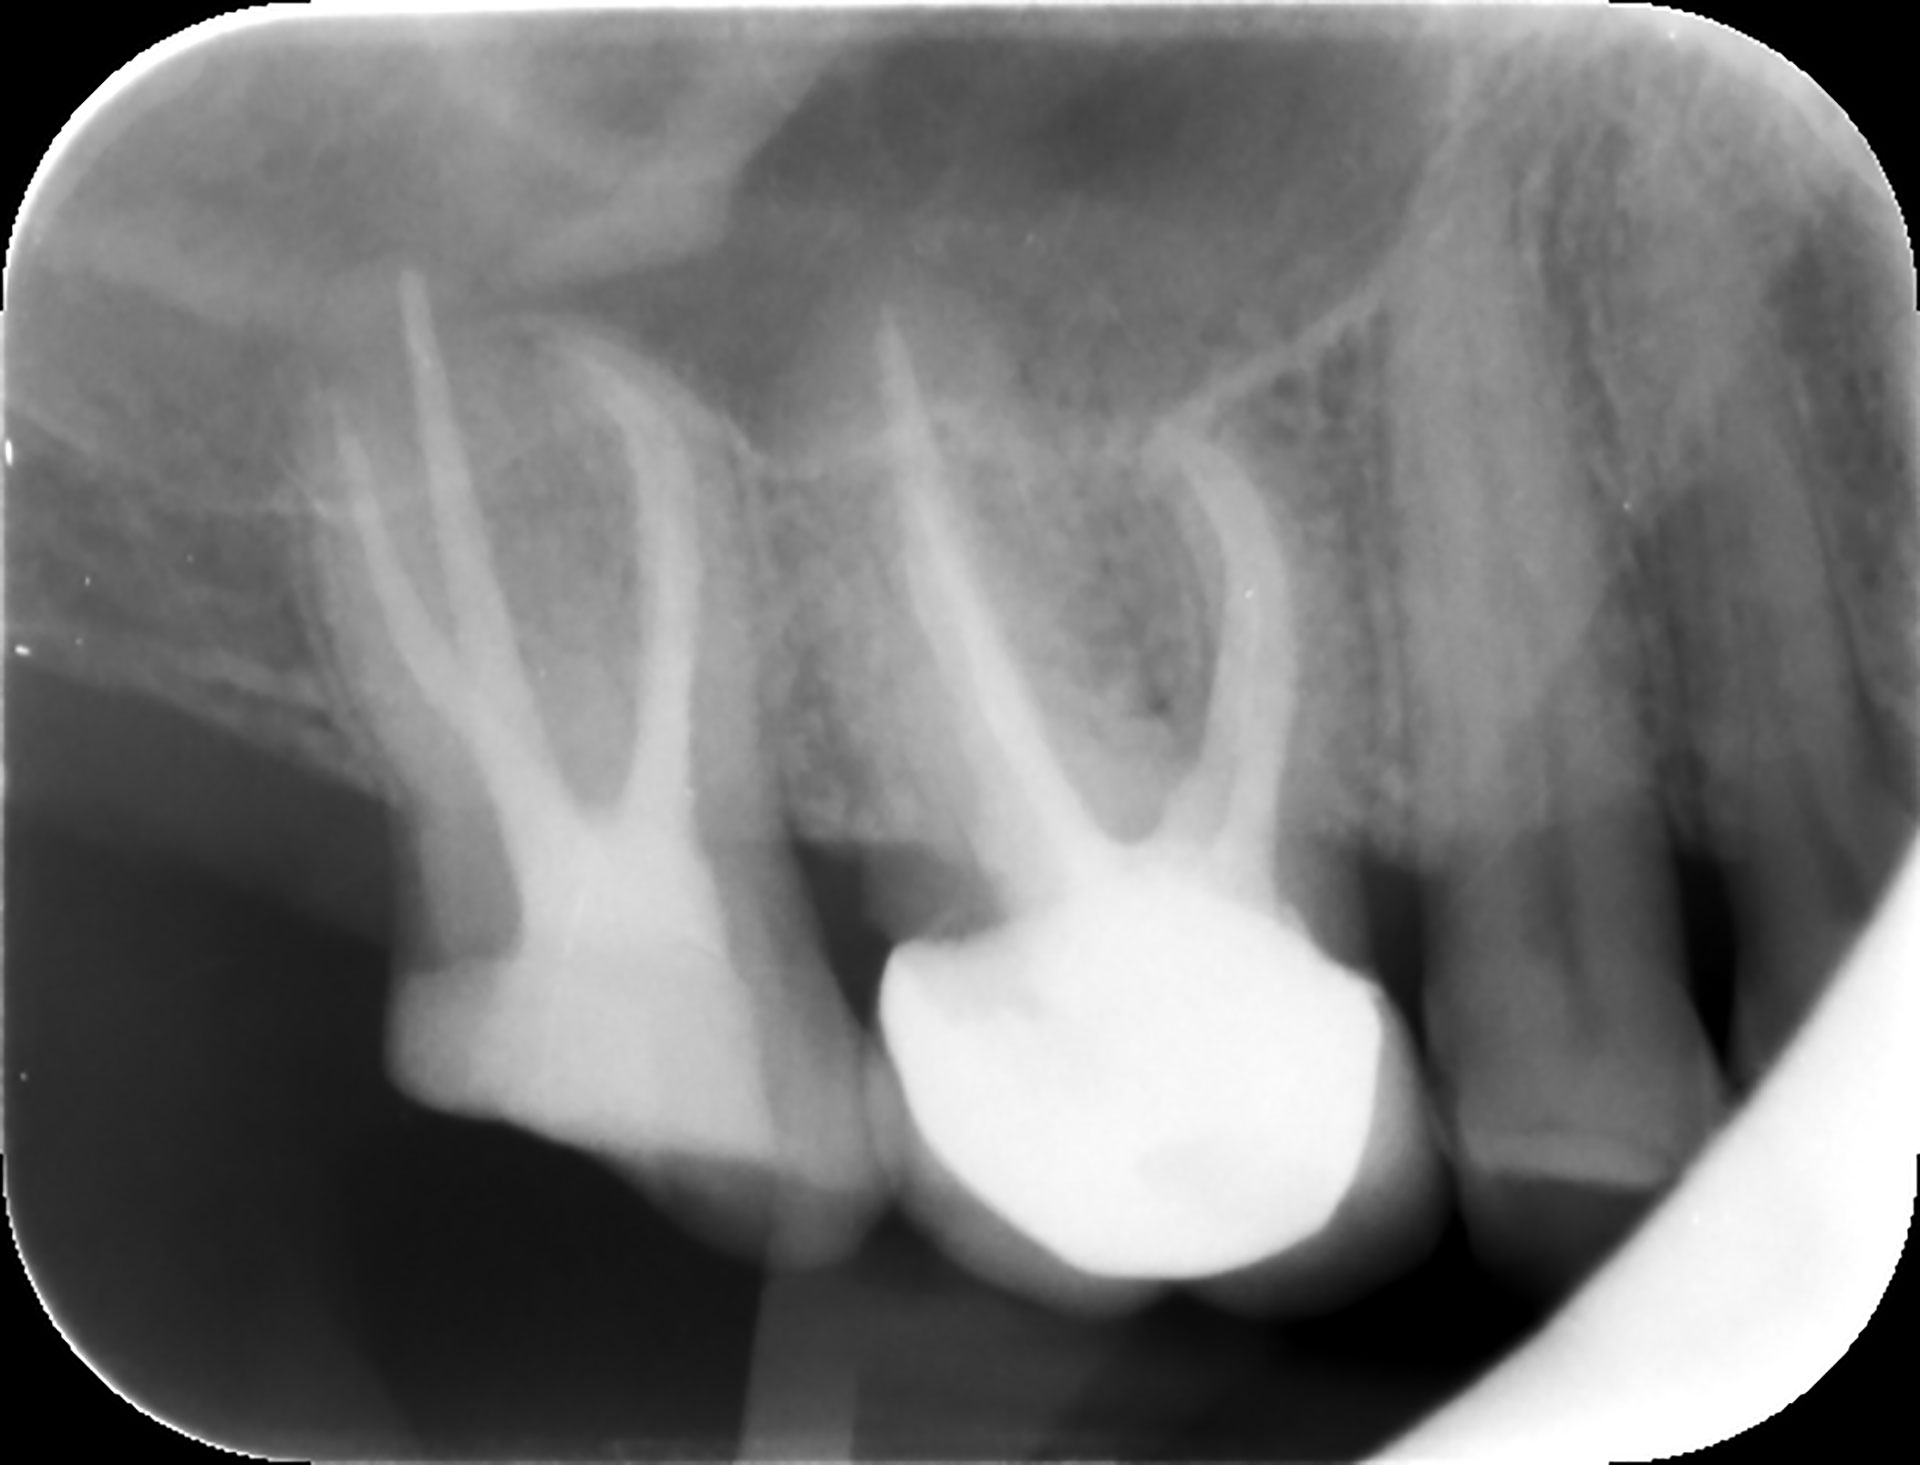

Postoperativ røntgen viser godt utført endodontisk behandling.